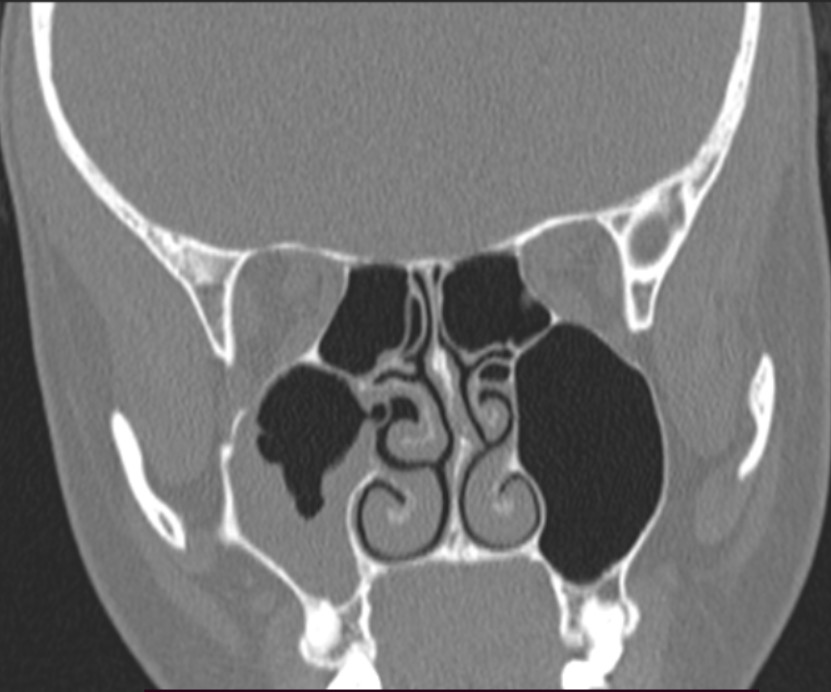

Симптомы ОРВИ появились давно, полагаю, что недолечилась и осложнение дало на нос. Обратилась к врачу Лору 30.08.2025 (пришла уже со снимком КТ (1)) он поставил диагноз - острый правосторонний верхнечелюстной синусит, легкой степени тяжести. Мои симптомы на тот момент были: головная боль, отдающая в пазух носа, температура 37,3, выделений из носа не было с обеих сторон, нос дышал, периодически была небольшая заложеность. Доктор выписал : Амоксиклав, Спрей Аквалор софт и Назонекс. Ушла лечится, на второй день приема антибиотиков у меня почему то поднялась резко температура до 38. Сбила на второй или третий день лечения. Промывая нос, капала. Сегодня делала повторный снимок КТ (2) и что то вообще без изменений, наверное больше увеличилось жидкости. Я в растройствах, так как не хочу делать прокол и думала, что мне первоначальное лечение поможет. Как быть сейчас? Возможно ли изменить лечение и попринимать что то еще, более действенное? Прошу помочь разобраться в этом вопросе.

P.S также доктор сказал, что у меня плохо дренируется правый пазух, на фоне искривленной перегородки.

Здравствуйте! По КТ сохраняется выраженный синусит справа, лечение антибиотиком и спреями пока недостаточно эффективно. В таких случаях обычно корректируют терапию (другой антибиотик, добавление муколитиков, физиотерапии), а при отсутствии улучшений рассматривают пункцию для дренирования пазухи. Рекомендую повторно обратиться к ЛОР-врачу для пересмотра схемы лечения.

Здравствуйте! На снимках действительно видно скопление жидкости в пазухе и при искривлённой перегородке дренаж затруднён, поэтому улучшения может не быть. Иногда удаётся обойтись без прокола, усилив лечение это  смена антибиотика, промывания пазух под контролем врача, добавление местных процедур. Но решение о тактике должен принять ЛОР после осмотра и оценки динамики.